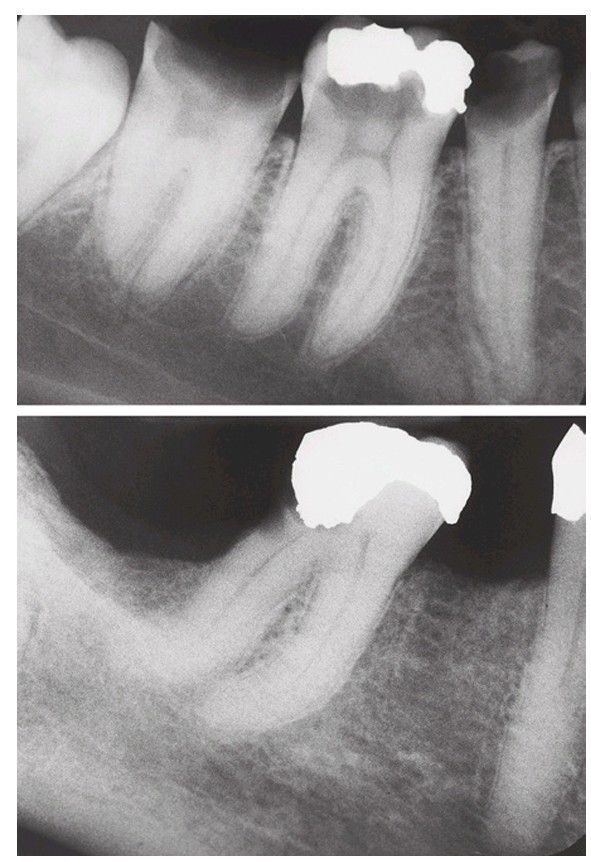

Difficult extraction case

Large caries or large restorations may lead to fracture of the crown of the tooth and thus to a more difficult extraction.